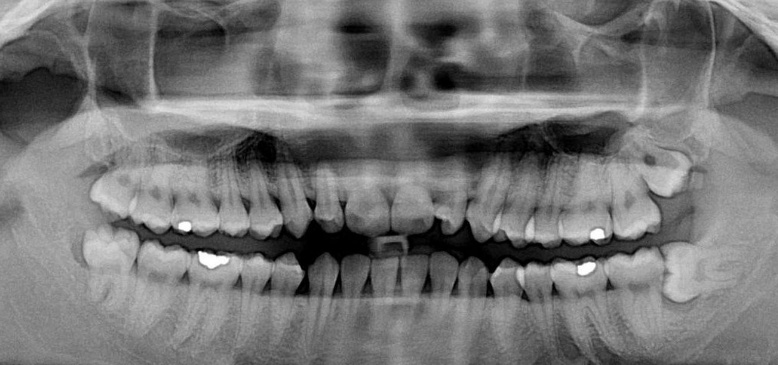

3、智齿缺失。

在人类的进化的道路,我们的大脑挤满了头骨,下颚缩小,没有留给第三磨牙(智齿)的空间了。并且在几千年前人类开始烹饪食物并发展农业之后,饮食变得更加柔软,不需要再咀嚼坚硬的食物。智齿的存在显得有点多余。大约几千年前,一种涉及PAX9基因的突变出现,导致患者第三磨牙(智齿)发育不全,智齿缺失。根据一项研究表明,韩国人的患病率达到了41%,也就是说10个韩国人里面,有4个是没有智齿的。